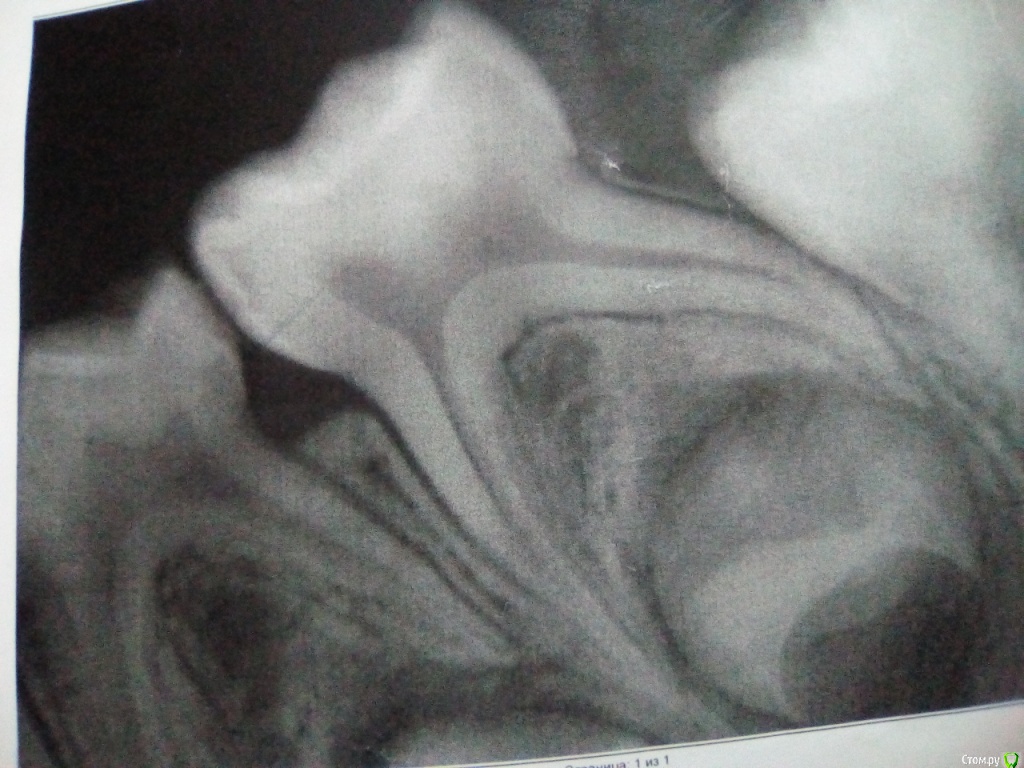

asie84 Опубликовано 2 сентября, 2019 Поделиться Опубликовано 2 сентября, 2019 Добрый день.Ребенку 6 лет.Были на осмотре у стоматолога, попросила посмотреть состоянии пломб на контактах между 4ми и 5ми снизу на обеих сторонах.На визуальном осмотре стоматолог ничего не отметила (о наличии проблем), сделали по моей просьбе рентген (рентген прилагаю, извините за качество, это распечатка).Так и не поняла есть ли там кариес или нет, стоматолог за лечение ничего не сказала, а на снимках какие то затемнения, боюсь упустить зубы(.Особенно волнует, что за темная полоса под пломбах на одной из четверок.Если вас не затруднит, посмотрите пожалуйста снимки Ссылка на комментарий

krokomot Опубликовано 3 сентября, 2019 Поделиться Опубликовано 3 сентября, 2019 Кариес есть, пломбы переделать, использовать зубную нить, чистка на ночь обязательно, поменьше сладкого. Ссылка на комментарий